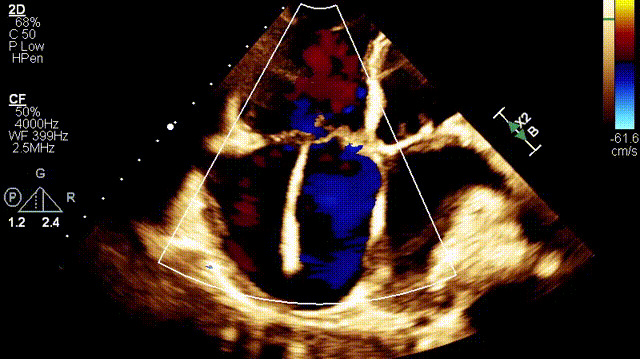

植入前超聲

接受治療的是一例89歲的超高齡女性患者,主訴“起搏器術(shù)后7年余,反復(fù)氣促4年”,因反復(fù)心衰失代償,胸腔積液就診。術(shù)前超聲提示:1.雙房及右室擴(kuò)大(右室舒張末和收縮末容積分別為55ml和21ml,右室FAC27%);2.三尖瓣瓣環(huán)擴(kuò)張(瓣環(huán)左右徑41mm,前葉長度21.3mm,隔葉長度15.2mm,后葉長度23.1mm),瓣葉閉合不攏;3.功能性重度三尖瓣反流(FTR 5+,收縮期三尖瓣口反流束縮流頸寬度21mm);4.下腔靜脈內(nèi)徑約25mm,呼吸塌陷率<50%;5.輕度肺高壓。術(shù)前CT結(jié)果顯示,入路血管最小平均徑約9.6mm,入路血管無嚴(yán)重迂曲、鈣化。隨后,王焱教授及其團(tuán)隊(duì)王斌教授、陳翔教授、超聲科蘇茂龍主任、手術(shù)室溫紅梅護(hù)士長進(jìn)行了詳細(xì)而周密的術(shù)前討論,最終選擇我國自主研發(fā)的LuX-Valve Plus經(jīng)血管三尖瓣置換系統(tǒng)對(duì)患者進(jìn)行手術(shù)。